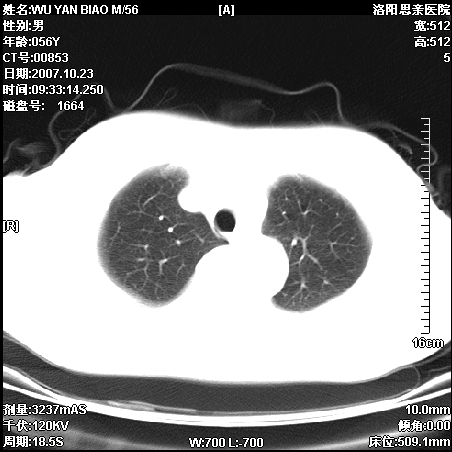

标题: CT10160:M56Y,体检发现,病人无不适,病人随访中 [打印本页]

标题: CT10160:M56Y,体检发现,病人无不适,病人随访中

后上纵隔占位,与肺交界清,宽基底附着脊柱,密度均匀,局部骨质无明确改变.

考虑;神经源性肿瘤,---起源交感n链?,不除外肠源性囊肿.

1、病灶在后纵隔脊柱旁沟内,此处是神经原性肿瘤的好发部位

2、病灶边缘光滑整齐,更说明病灶来于纵隔,由于有胸膜的包裹所以才导致这么光滑的边缘

3、病灶内的密度均匀